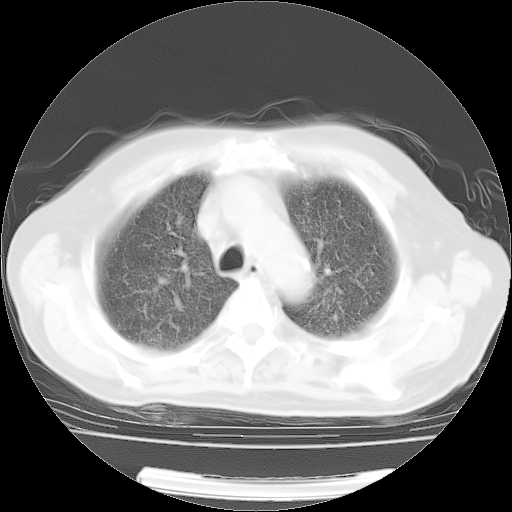

4月14日肺部CT

楼主| 发表于 2010-4-28 16:51 | 显示全部楼层

楼主| 发表于 2010-4-28 16:53 | 显示全部楼层

肺部CT平扫未见异常。